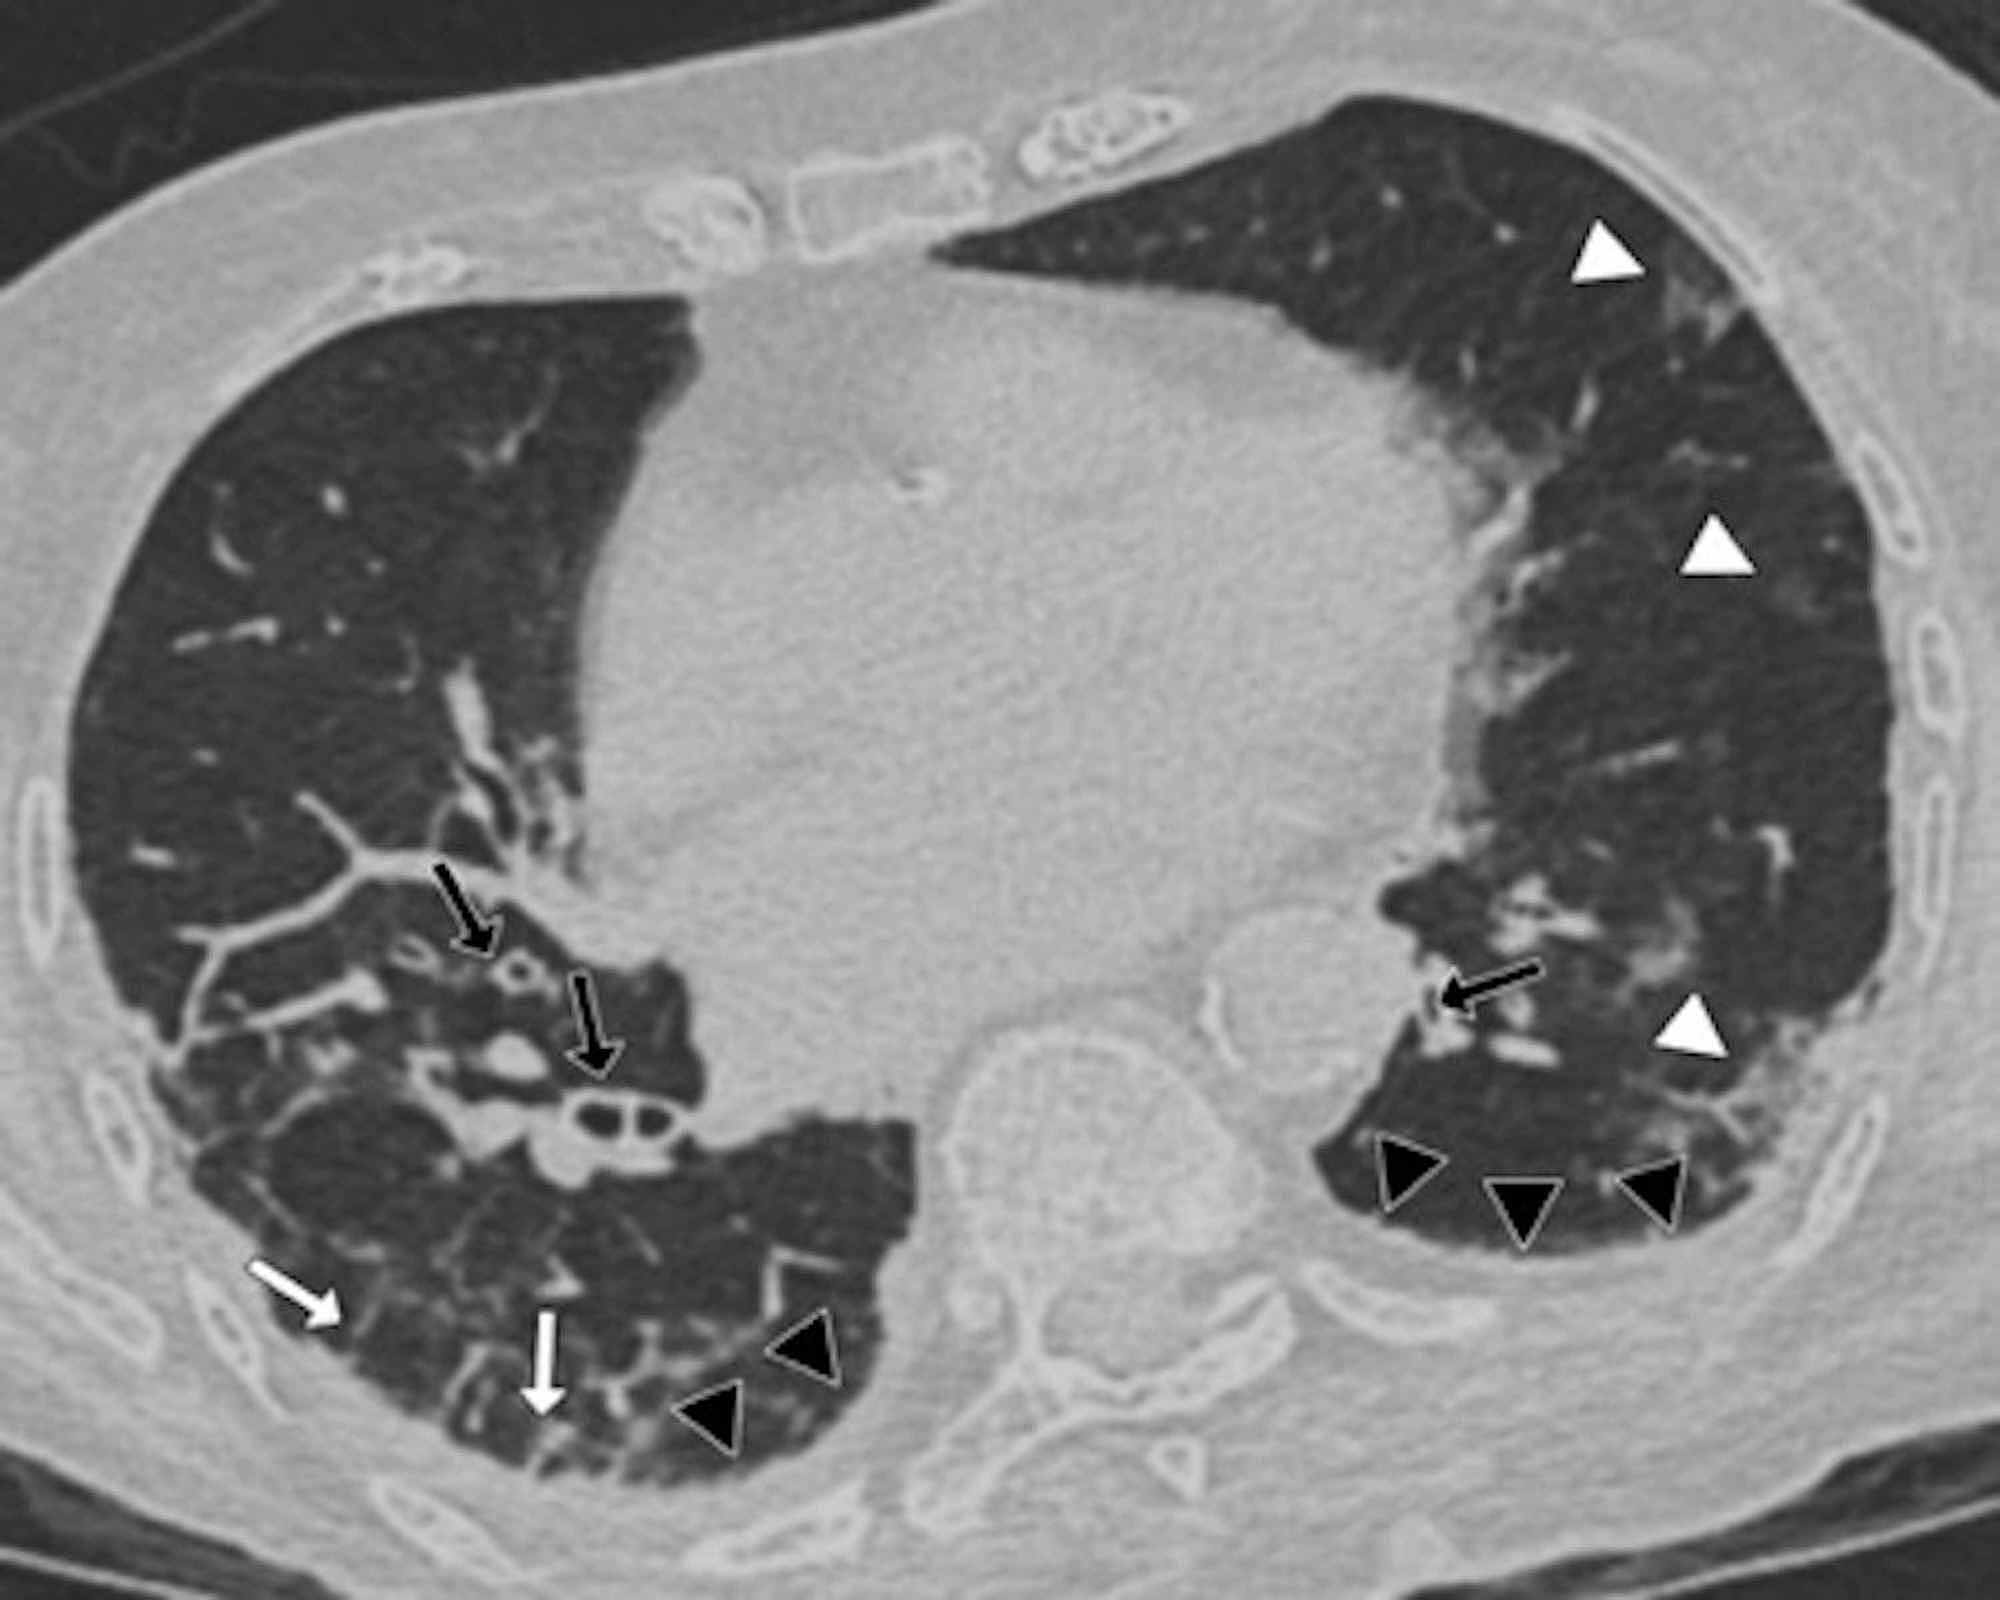

The distinctive CT features in our cohort are summarized in Table 3, including GGO and consolidative patchy mostly amorphous (72%) lesions, bilateral posterior and peripheral multi-lobar lung involvement, pleural effusions, subpleural fibrotic lines, subpleural sparing, vascular engorgement, occasional crazy paving, occasional mediastinal lymphadenopathy, pleural thickening, lack of cavitation, and absence of reverse halo (atoll) signs.

Subpleural sparing, which was observed in this patient cohort, has never been reported before, whereas mediastinal lymphadenopathy has been reported occasionally in the literature in English [11]. Focal vascular engorgement, septal thickening, and a subpleural fibrotic line were seen frequently in our cohort, with frequencies of 83%, 72%, and 61%, respectively.

Patients’ CT features are presented in detail in Figures 3, 4, 5, 6, 7, 8. A majority of cases (56%) had moderate severity scores. There was no correlation between the severity score and mortality, p=0.790 (Table 4).